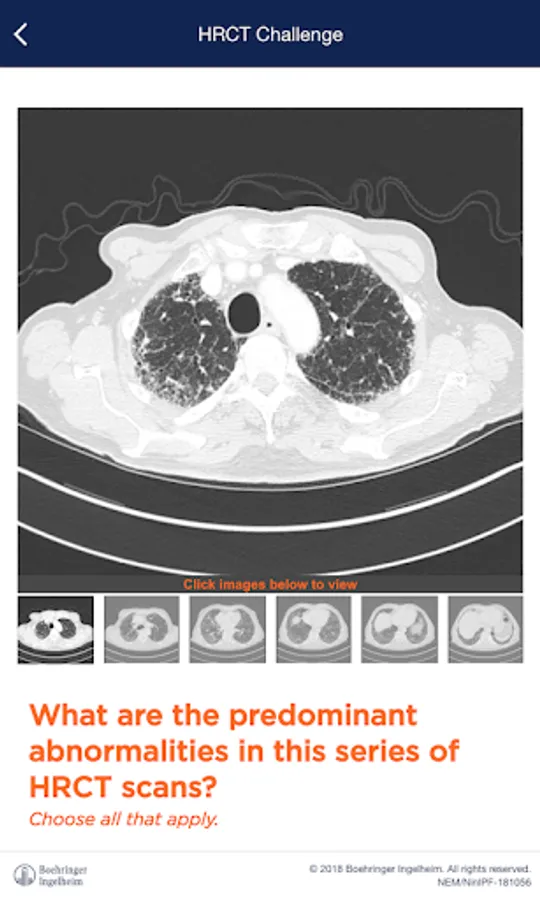

IPF Experts is an application that provides insights about IPF disease to healhcare professionals. IPF Experts consists of IPF information, online videos, visual and audial challenges, risk assessment calculator, congress calendar and further features.

IPF Experts Screenshots